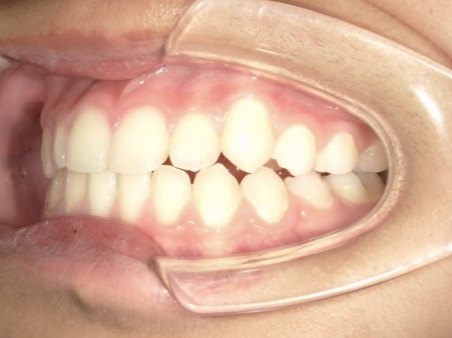

治療中⑦ 中1:12y11m

モノブロック装置継続中、左上八重歯の改善中